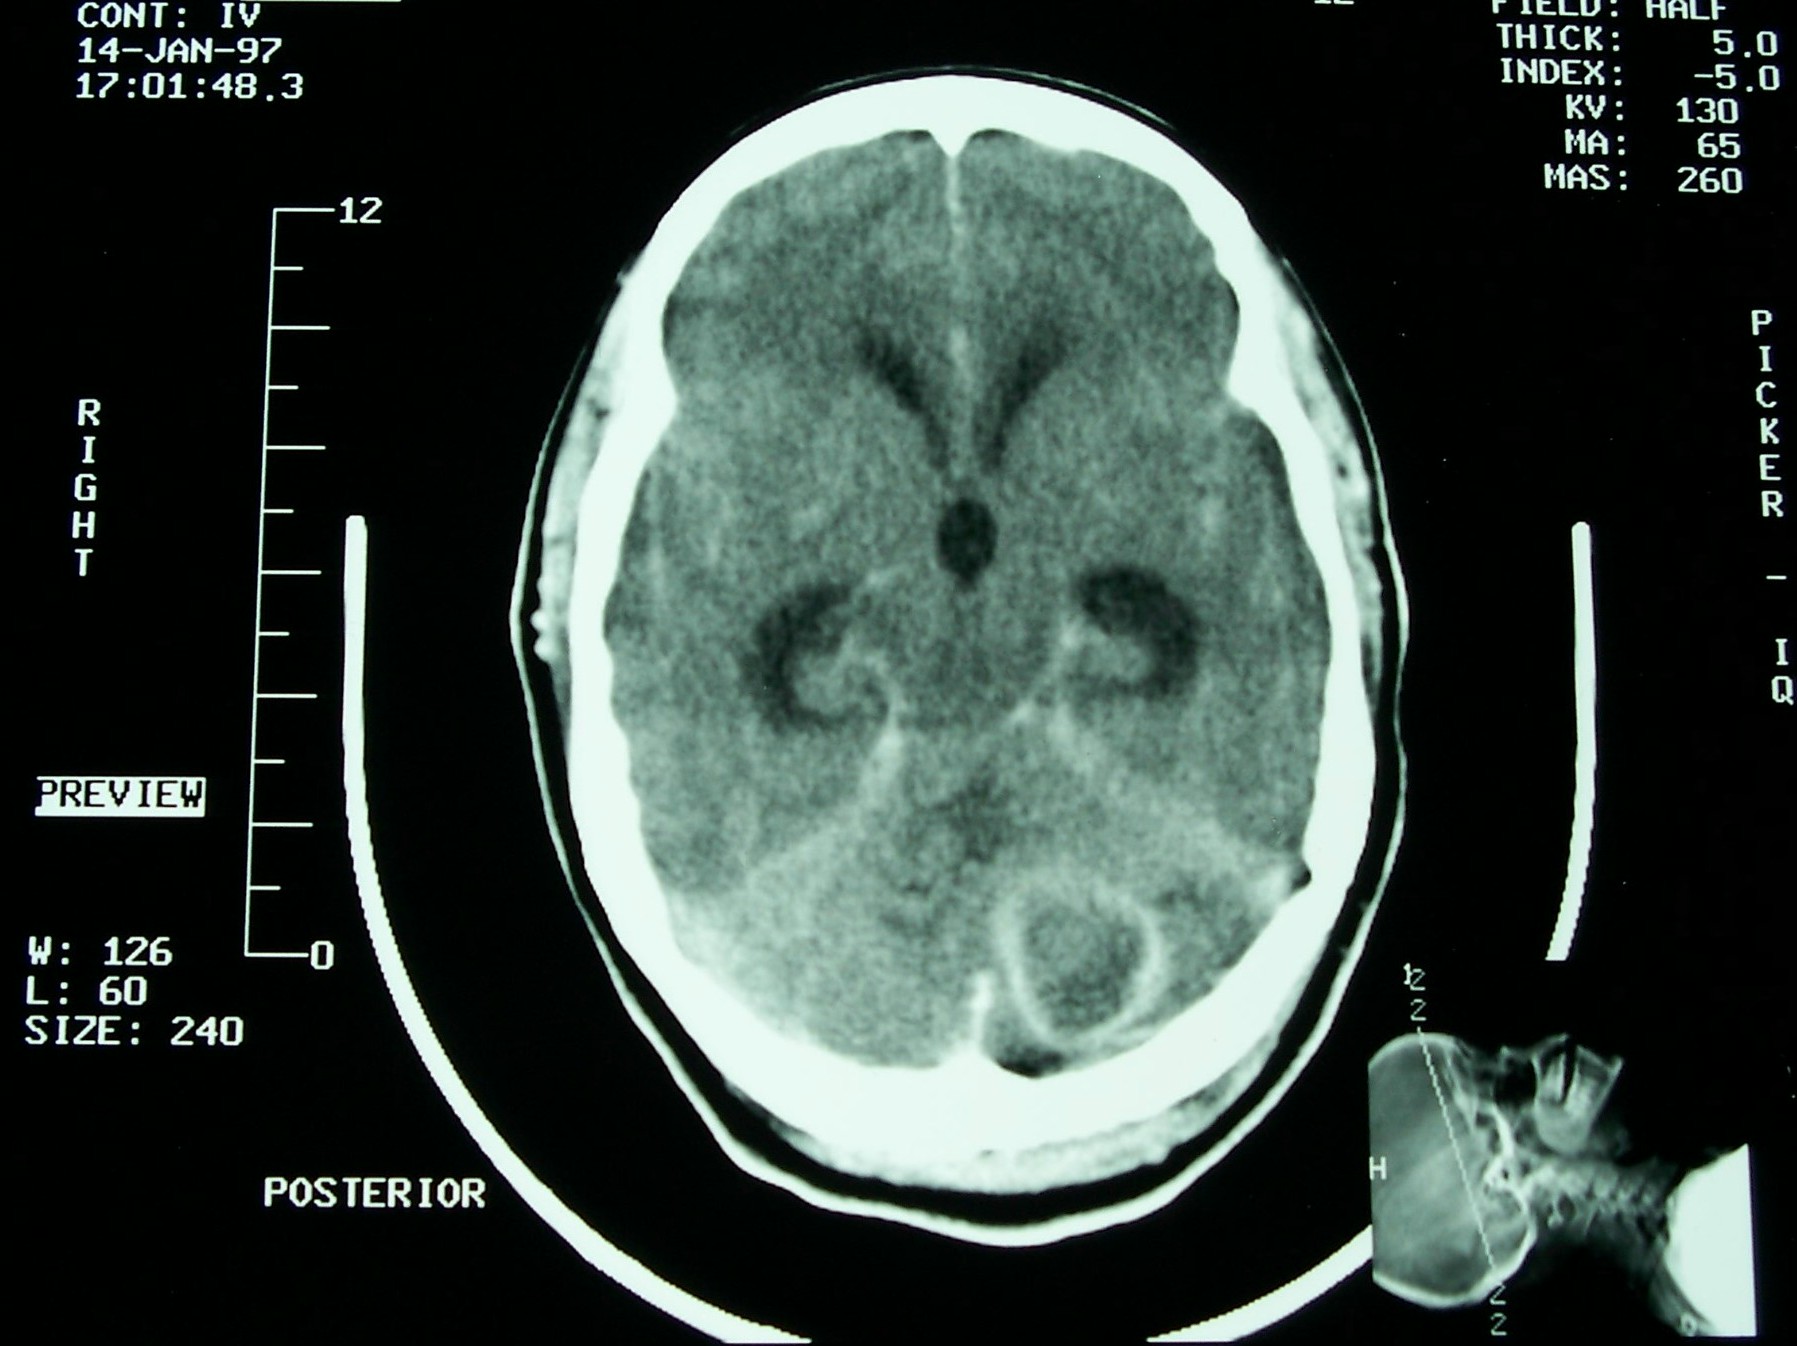

LJ Fullerton - Brain Surgery January 14, 1997